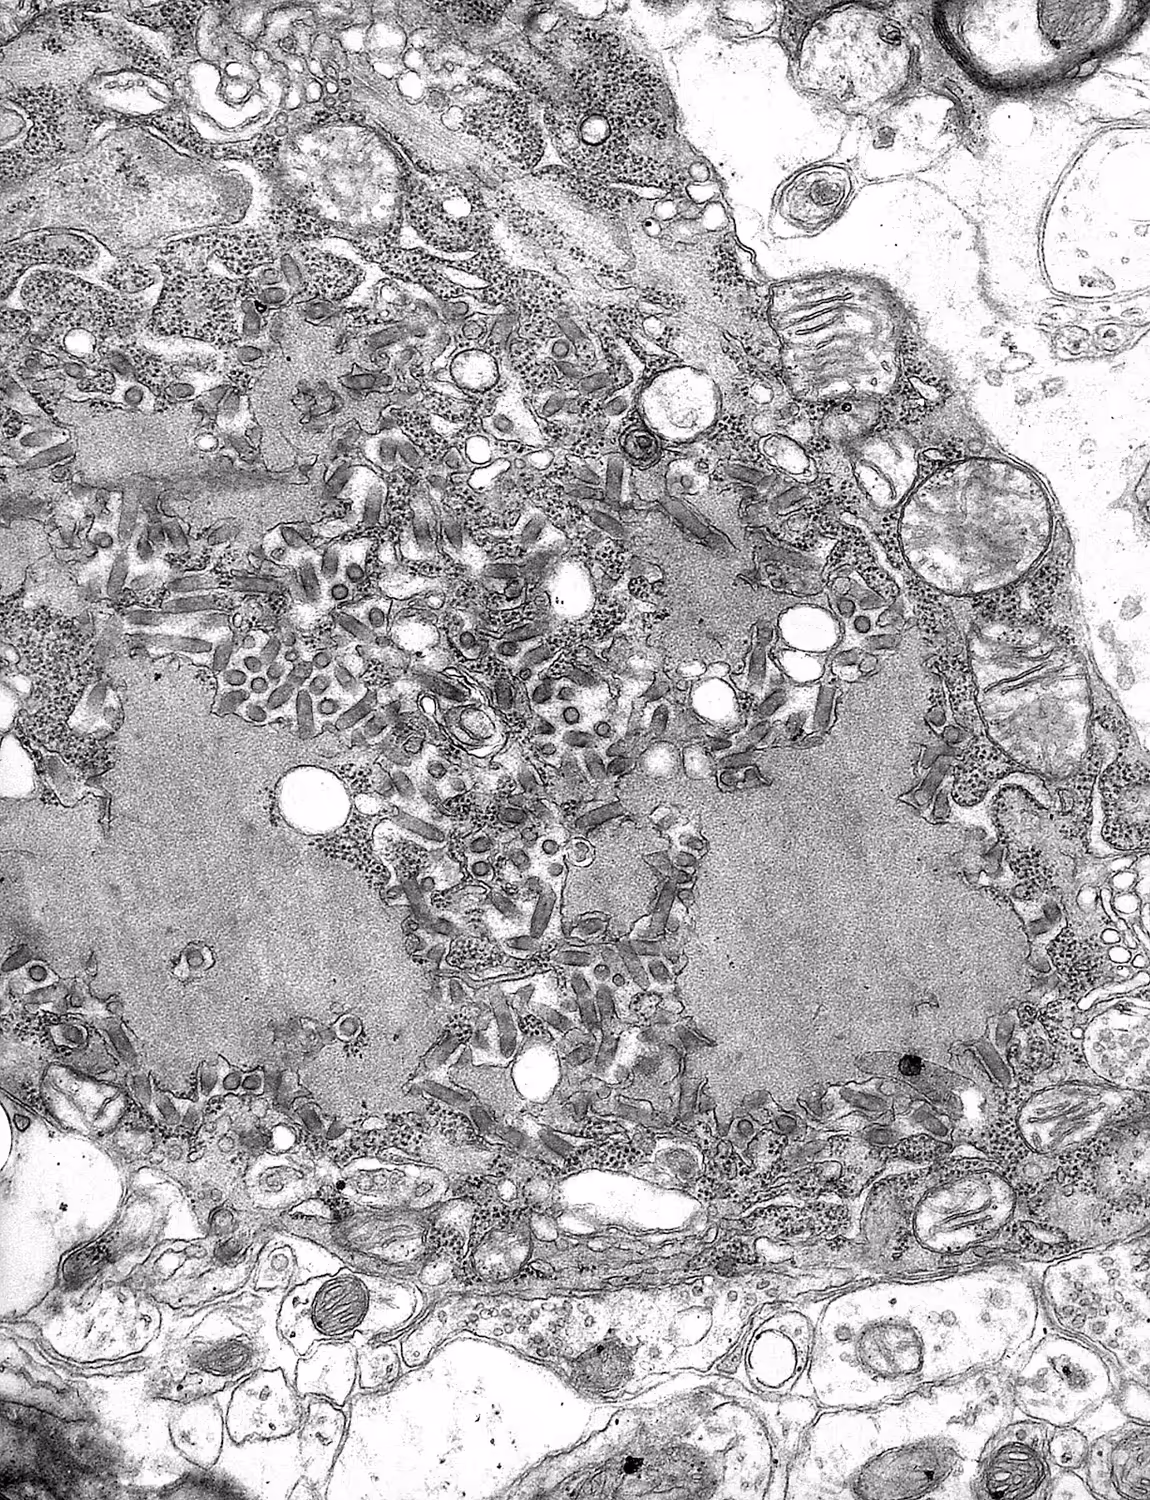

Weil die Symptome mit denen einer Tollwut-Infektion übereinstimmten, hatten die Spitalmitarbeitenden bereits vor dem Tod des Mannes Experten des Gesundheitsministeriums von Ohio und der US-Gesundheitsbehörde CDC hinzugezogen. Die Analyse von Speichel-, Nackenhautbiopsie-, Serum- und Liquorproben untermauerte den Tollwutverdacht. Nach dem Tod genommene Hirngewebeproben bestätigten den Verdacht schließlich: Der Mann war an Tollwut gestorben. Dies jedoch, ohne dass er oder seine Familienmitglieder von Tierkontakten berichteten.